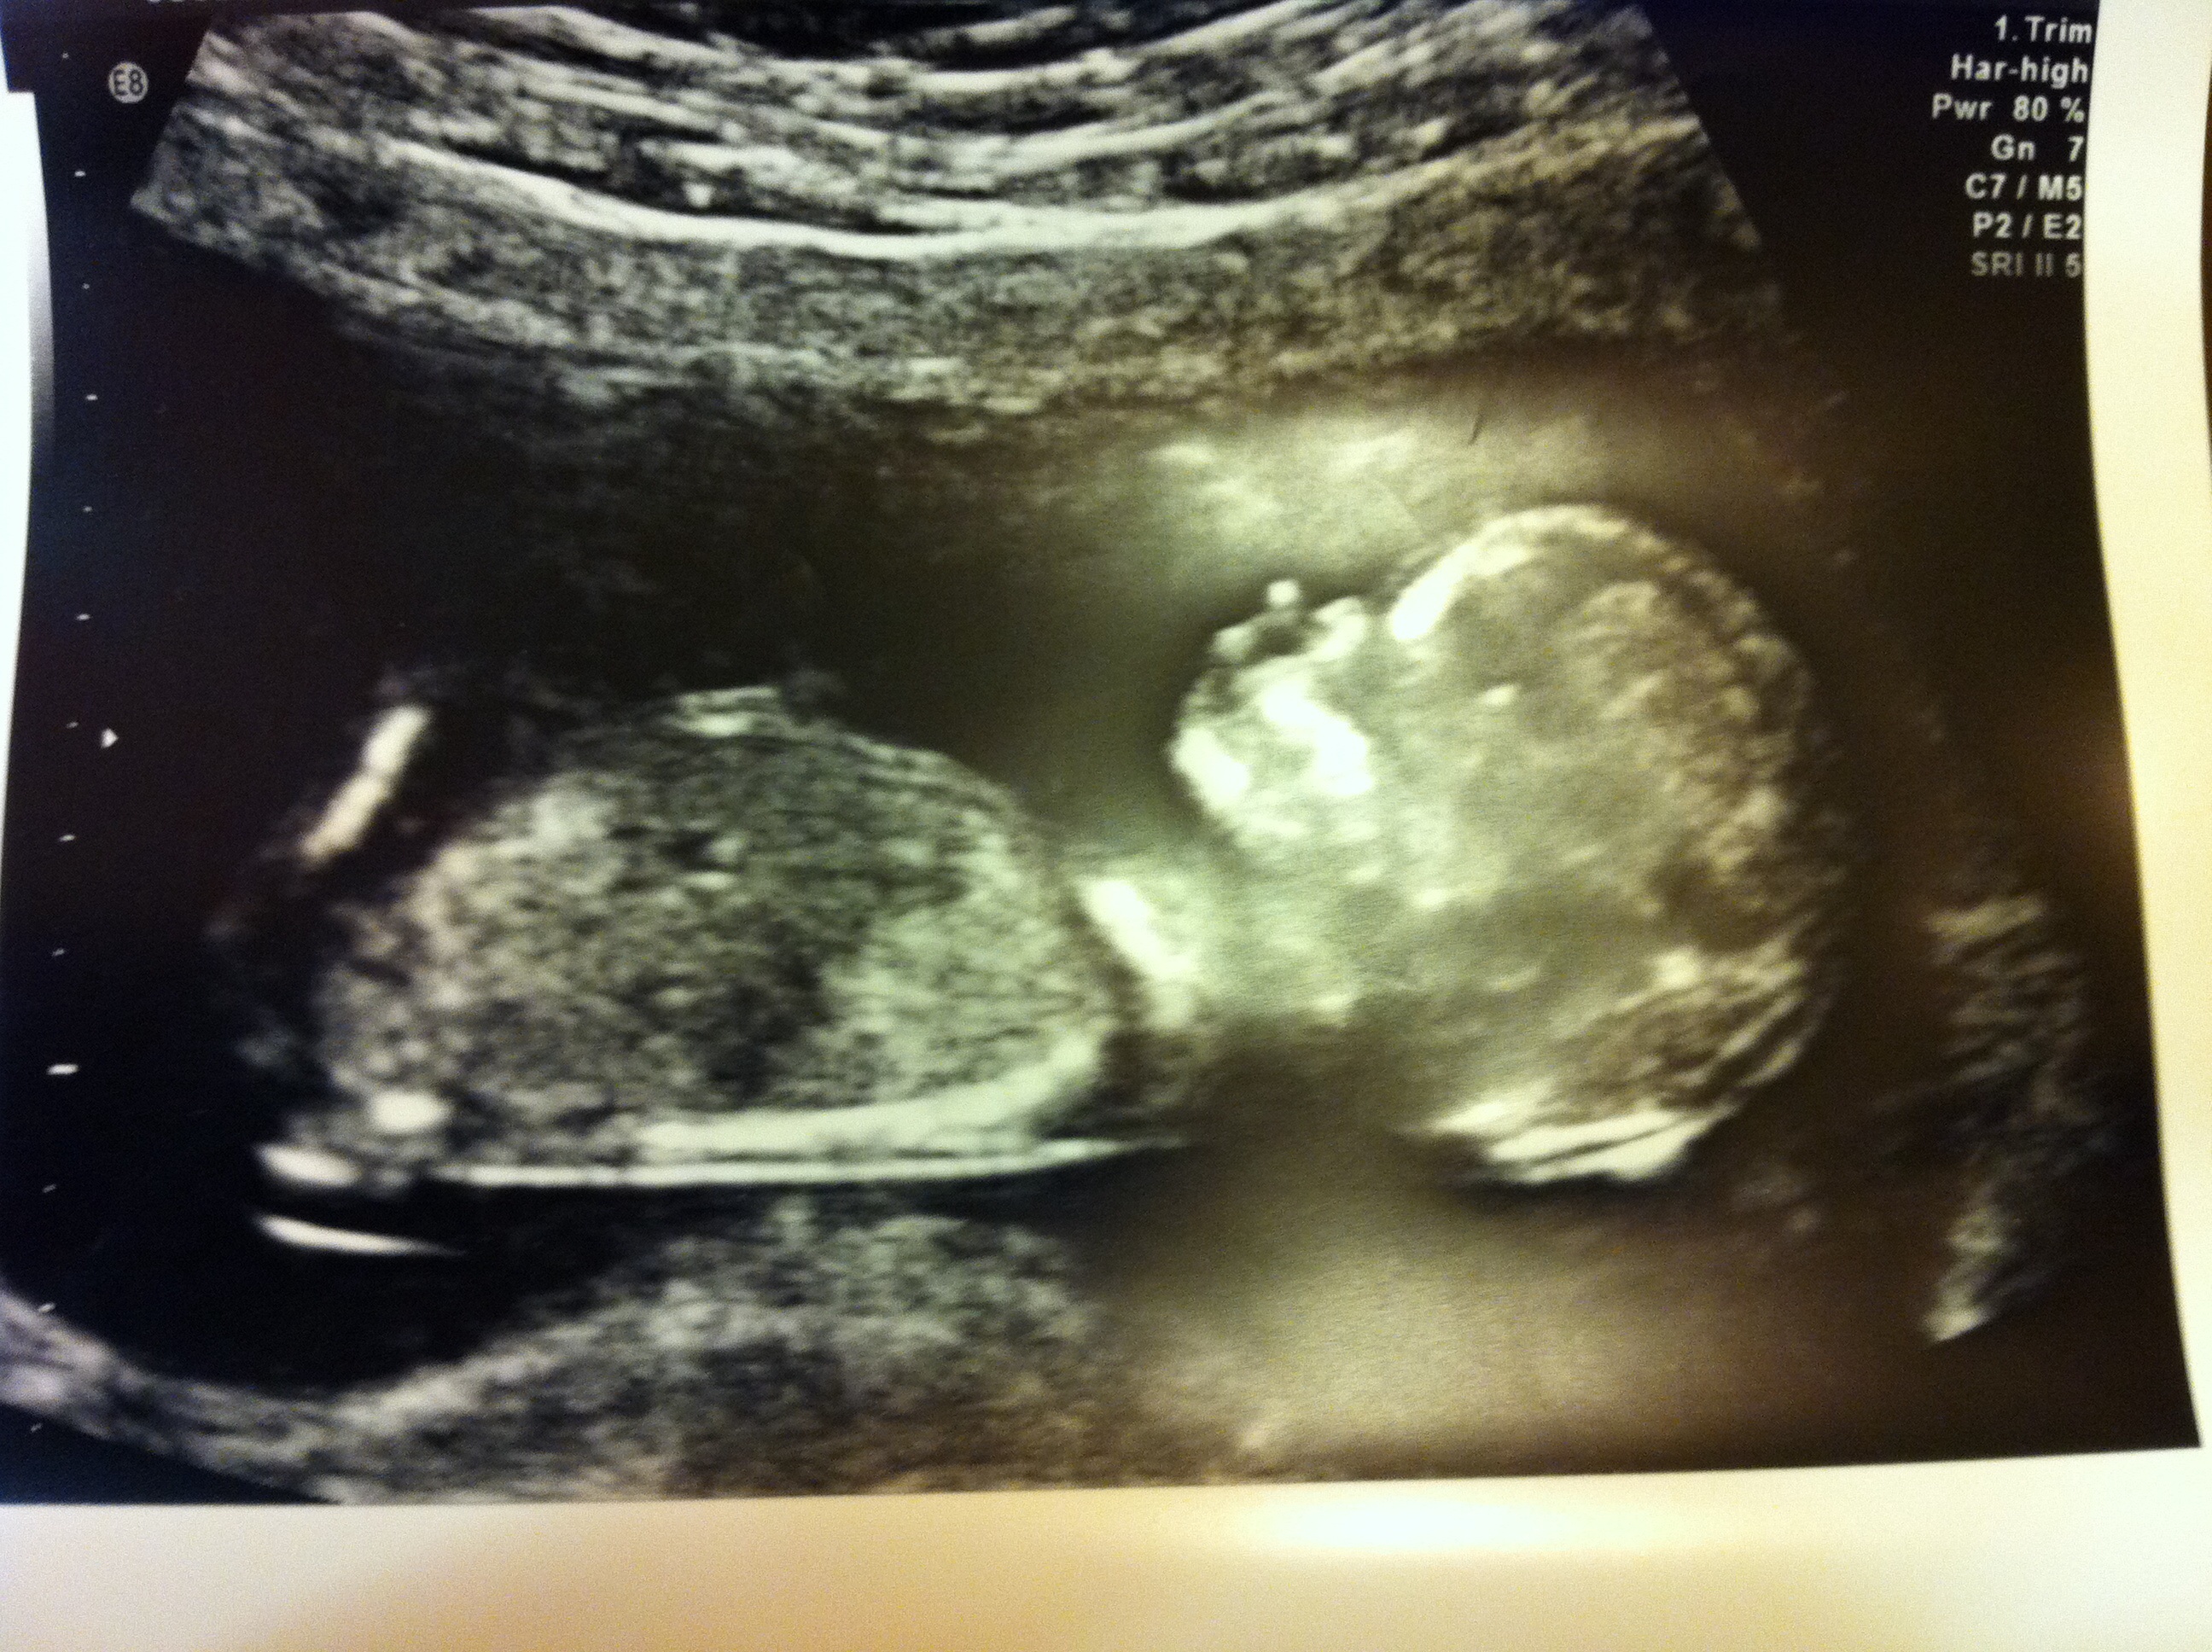

The nub is circled in the 2nd pic and you have a sweet little boy there.

I could definitely be wrong but it looks like it starts where you circled then continues riding to the left with a bulb at the end which means boy. A girl would have a more parallel nub with a fork at the end.

Looks like a little boy - nub is on the rise. How far along are you? x

Kasey the scan was took at 13+2. I see what you mean Abi but it looks like 2 completely different lines in the first pic do you agree? I've had crap nub shots on all my scans lol